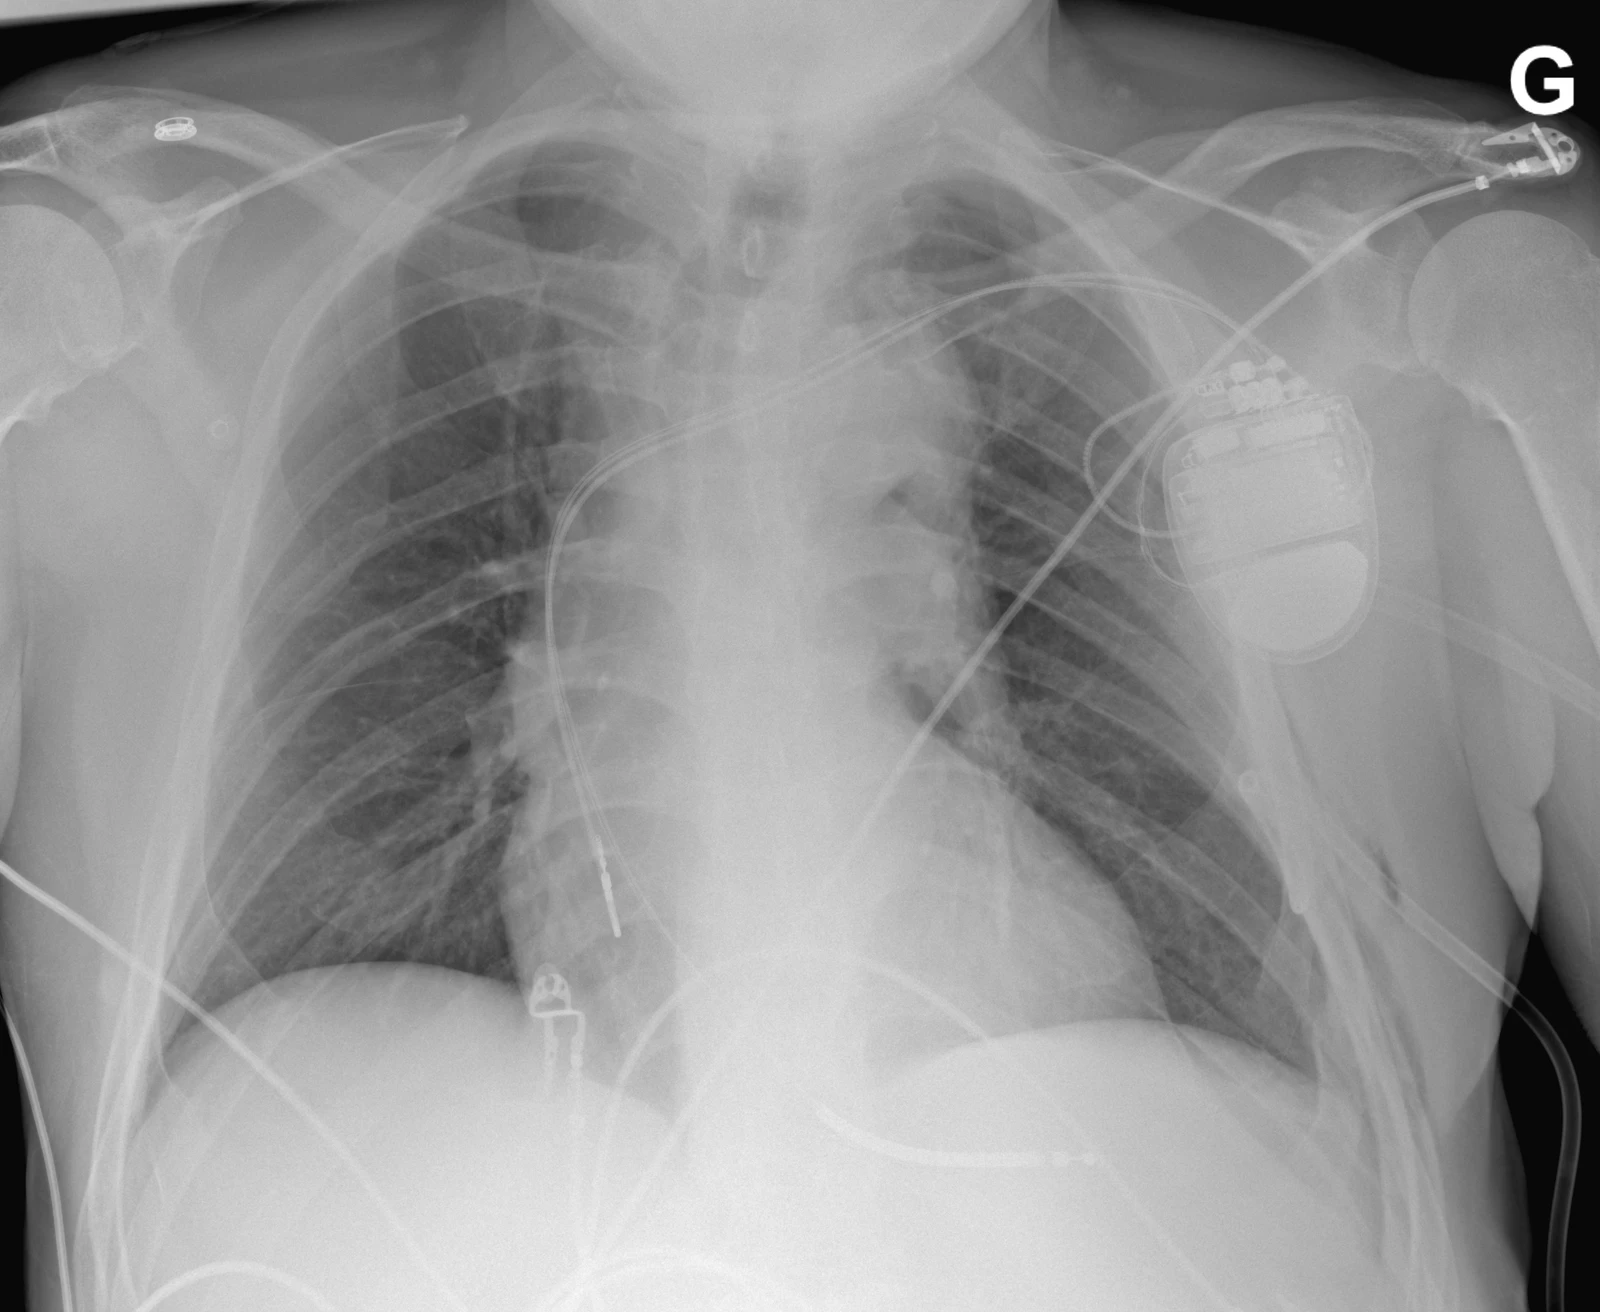

Cette radiographie du thorax a été faite chez un patient se plaignant de douleur thoracique gauche quelques heures après la pose d’un pacemaker (PM). Plusieurs complications peuvent survenir après la pose d’un PM. Le pneumothorax est une complication de l’accès vasculaire lors de l’implantation avec une fréquence de 0.9-1.3%. Les facteurs de risques sont l’âge (> 80 ans), sexe féminin, BPCO sous-jacente, PM double chambre. Le pneumothorax est une complication qui survient durant la pose du PM mais peut ne pas être reconnue immédiatement. Les patient·es se présentent avec des douleurs thoraciques respiro-dépendantes ipsilatérales au boitier du PM et une dyspnée.  Le traitement dépendra de la taille du pneumothorax et des comorbidités de la ou du patient·e. Les petits pneumothorax (< 2 cm) sont plutôt traitement conservativement. En général, un pneumothorax de > 2 cm devra être drainé.